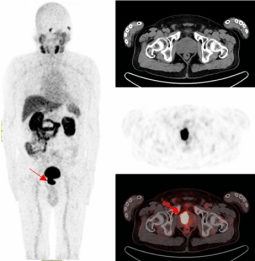

一名69岁的男性患者因常规体检发现血PSA明显升高后,辗转多家医疗机构,复查两次血PSA、一次盆腔MR平扫+增强,两次前列腺穿刺活检,均被确诊为前列腺结节性增生。

既无肉眼血尿,又无排尿异常,更没有腰酸背痛,但多次血PSA结果异常。患者遂来到污污漫画

附属医院核医学诊疗中心接受了68Ga-PSMA-PET/CT检查,结果显示前列腺的确存在良性增生,在结合PET/CT核素影像诊断进行靶向穿刺精准定位后,最终确诊为前列腺腺癌。

前列腺一旦发生癌变就会特异性表达前列腺特异性膜抗原(PSMA),其作为近年来国际上最新的靶向前列腺癌的分子靶点,68Ga-PSMA PET/CT对于前列腺癌的检测在敏感性、特异性、阳性检出率上均高于传统检查手段,对原发灶和转移灶检出率可达到95%,对前列腺癌精准地早期发现、早期诊断,让患者少走弯路。